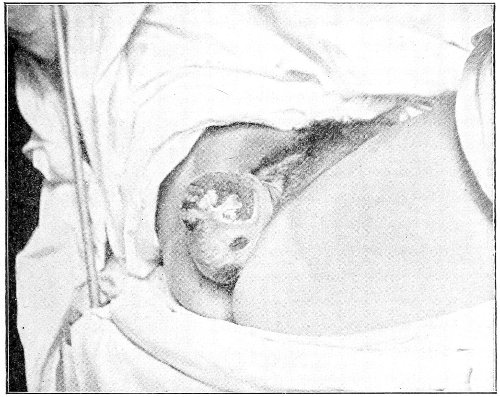

Suppuration of the vulvo-vaginal gland is accompanied by marked swelling and peripheral edema. The swelling may extend to the anus, and is of characteristic shape (Fig. 17). The pain is always severe. Fluctuation is first apparent on the inner surface of the labium majus. If the condition is not treated, one or more fistulous openings appear below the orifice of the duct, and the pus is discharged. The condition then becomes chronic. The fistulous openings persist. Acute inflammation disappears from the gland, leaving it in a condition of hypertrophic induration. A thin, milky or greenish, purulent fluid may be pressed out of the duct or the fistulous openings. Infection from this discharge may be communicated to man, or may ascend the genital 40 tract, producing inflammation of the endometrium or of the Fallopian tubes.

Fig. 17.—Abscess of right vulvo-vaginal gland.

In abscess of the vulvo-vaginal gland a free incision should immediately be made into the labium at the junction of the skin and the mucous membrane. The interior should be wiped out with pure carbolic acid and the cavity packed with gauze. If the disease is first seen in the chronic stage, after the abscess has evacuated itself, the only method of cure is to excise, with curved scissors, the whole of the indurated gland, the duct, and the fistulous tracts. The wound may be left open and packed, or it may be closed immediately with buried catgut sutures.